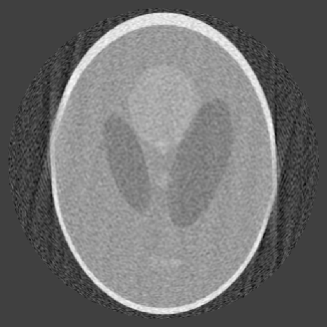

For our first numerical example, we use the classical head phantom of Shepp-Logan [17]. This phantom is shown in Figure 2.

The left figure is the original phantom. The right figure is the reconstruction by OPED based on the full data with , which means 251 views with angles equally distributed over and 251 rays per view, and the size of the reconstruction is pixels. Reconstruction based on the full data has been discussed in [4, 20, 21], we will not give further details here as our purpose is to demonstrate the feasibility of our method on the limited angle problem.

For the reconstruction on the limited angle data, we choose the same set-up, with 201 angles over and 201 equally spaced parallel rays in each view.

In our first example, , which amounts to data limited in an angle of about ; in other words, views from about angle are missing. The reconstruction by our algorithm is given in Figure 3 in which and for the left figure and for the right figure.

The left image is reconstructed with and ; it is a fairly accurate reconstruction, although there are noticeable artifacts in the direction of missing views and a bit distortion around two spots on the edges. The right image is reconstructed with and ; it shows clearly artifacts of ripples, but the image appears to be sharper and has less distortion than the one in the left otherwise. In the case of , the maximum of the condition numbers of the matrices is 160, so that the matrices are rather well conditioned. In the case of , the maximum of the conditions numbers is , which may have contributed to the ripples in the image.

The condition that guarantees the non-singularity of the matrices in this case is , whereas our computation of eigenvalues shows that has to be much smaller in order that the matrices are well conditioned. For our other examples, we will mostly take . The choice of means that our sampling of coefficients follows a curve that decreases from 1 to 0.9, a decline that is rather mild, which leads to reasonable reconstruction image.